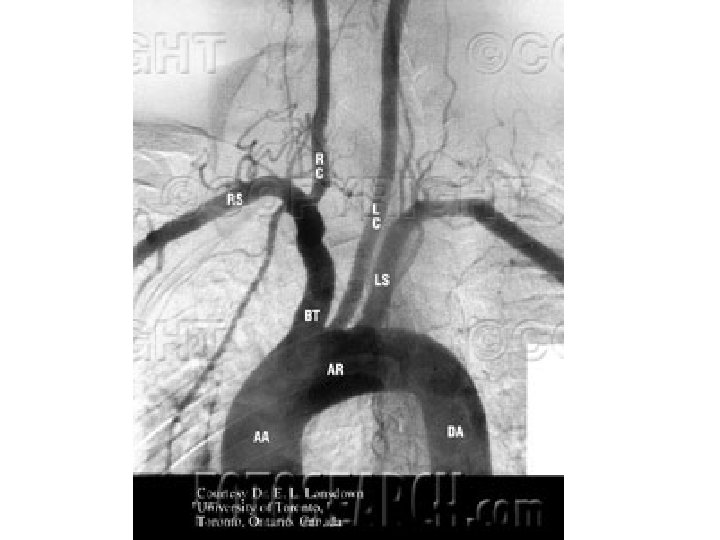

Subclavian steal syndrome • clinically significant reduction in blood supply to brain stem and cerebellum • reversal of blood flow through a. vertebralis due to occlusion/ stenosis of central part of AS or TBC • symptoms: vertigo, syncope, intermittent claudication of involved upper limb

Arteria subclavia • sulcus arteriae subclaviae pulmonis • apertura thoracis superior • sulcus arteriae subclaviae costae primae • fissura scalenorum • thoracic outlet syndrome • subclavian steal syndrome (a. vertebralis)

Arteria subclavia